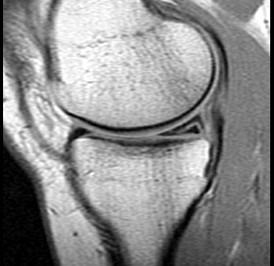

问题 男,29岁,左膝关节有外伤史,膝关节疼痛,活动受限,请结合所提供的图像,选择最佳选项 ( )

选项 A、内侧半月板内侧撕裂 B、后十字韧带撕裂 C、前十字韧带撕裂 D、内侧半月板外周后角垂直撕裂 E、未见异常

答案 A